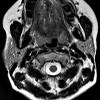

МРТ слюнных желез

Магнитный резонанс слюнных желез. Томографическое сканирование желез полости рта радиоволнами в сильном магнитном поле. В большинстве случаев патологические процессы поражают крупные слюнные железы (подчелюстные, сублингвальные, околоушные), поэтому именно они чаще всего проходят МРТ-сканирование. МРТ слюнных желез проводится для уточнения данных других методов инструментальной визуализации: ультразвука и сиалографии. Исследование помогает с высокой степенью точности дифференцировать опухолевые образования слюнных желез, воспалительные заболевания (scialadenitis), слюнные камни, кисты, гиперплазию или атрофию паренхимы и ; В целях более детального изучения опухолей, определения размеров и распространенности, дифференциальной диагностики доброкачественных и злокачественных опухолей, магнитный резонанс слюнных желез проводится с контрастом.